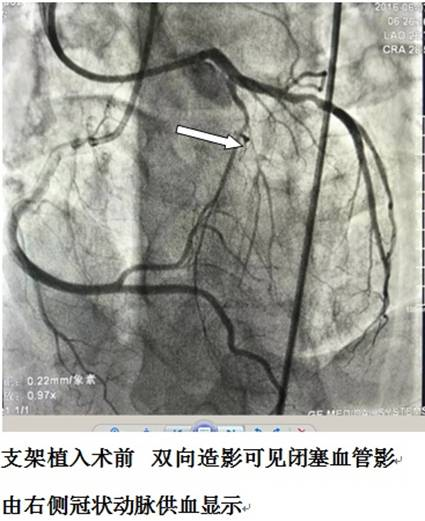

近日,中山一院外派我院的胡洵医师在为一位活动后胸痛的病人行冠脉造影检查时,发现这位患者冠脉病变为冠状动脉慢性完全闭塞病变(chronic total occlusions,CTO)。CTO是当前介入治疗的难点之一,冠状动脉慢性完全闭塞病变是指冠状动脉100%闭塞且闭塞超过3个月的病变。CTO病变行介入治疗(PCI)技术难度大、即刻成功率低、术后再闭塞和再狭窄发生率高,被认为是目前PCI领域最大的障碍和挑战,是对术者体力、耐力极限的挑战。然而成功开通CTO病变部位可缓解患者心绞痛症状,改善左室功能,稳定心肌的电活动,进而增强患者对未来冠脉事件的耐受力。

为保证疗效,胡洵医师与患者及其家属进行了充分沟通,最终决定迎难而上,为患者行PCI术。术中,胡医师展现了高超的PCI技术水平,虽然身穿厚重的铅衣,但动作轻盈而细致,经过近2个小时的奋战,终于为患者打通闭塞血管,恢复血流。经过精心护理与观察,患者术后运动耐量明显改善。